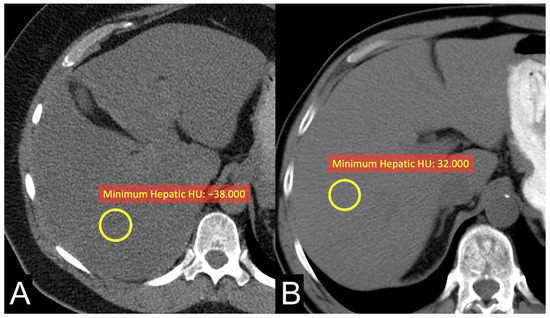

| Hepatic HUs | |||

| Median | 60 (49, 64) | 62 (48, 66) | 0.9 |

| Minimum | 16 (0, 26) | −4 (−23, 10) | 0.039 |

| Maximum | 104 (90, 122) | 108 (100, 130) | 0.2 |